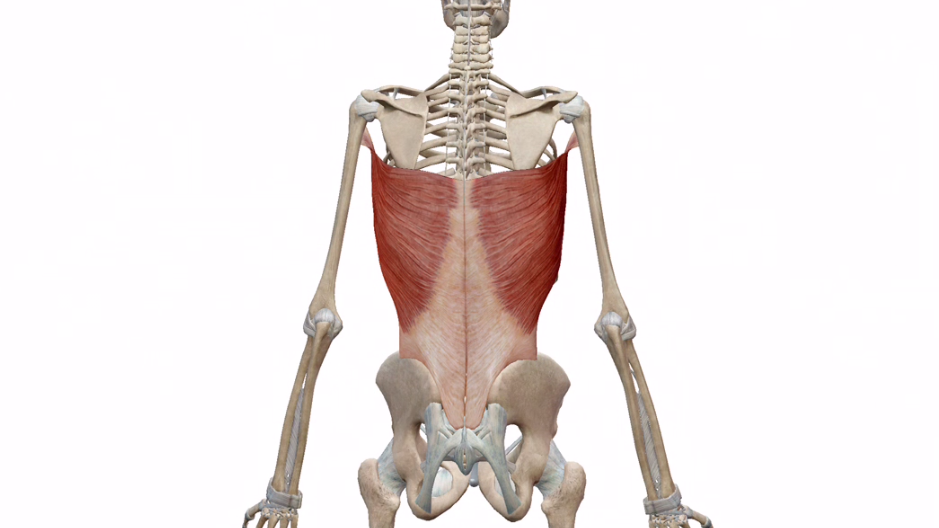

広背筋ってこんなやつです。

こんなやつです。